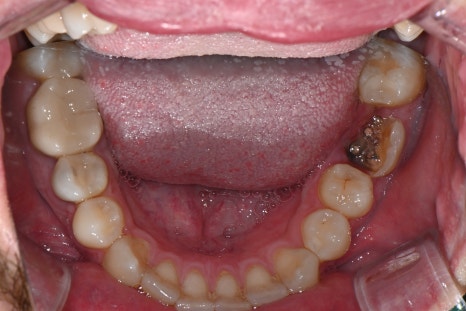

내원 당시 촬영한 위 아래 구강 내 사진입니다.

오른쪽 위 두번째 작은어금니의 상실로 임플란트 치료가 필요한 상태였습니다.